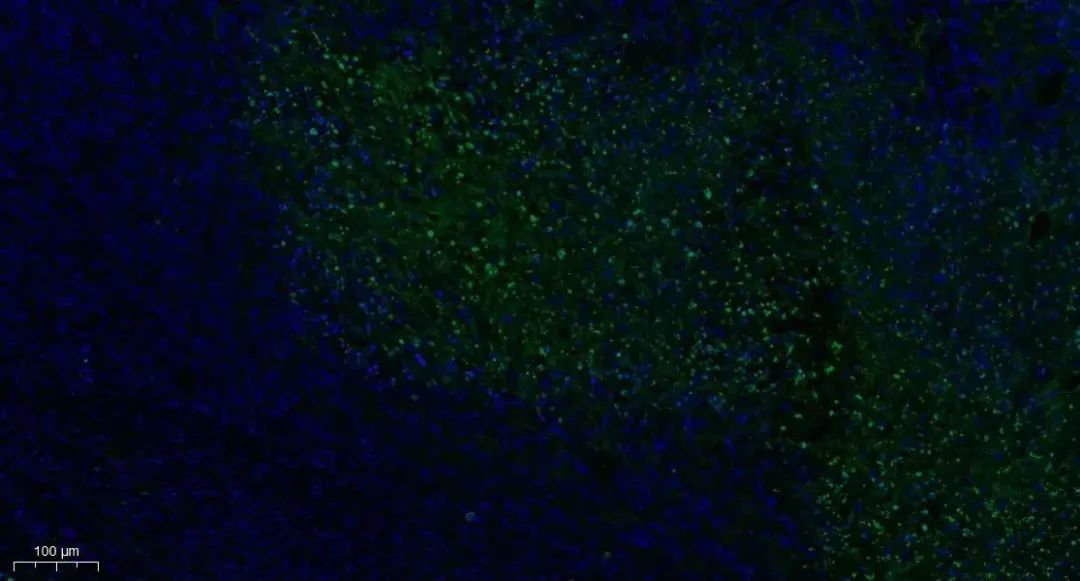

Tunel染色

细胞凋亡中, 染色体 DNA 双链断裂或单链断裂而产生大量的粘性 3'-OH 末端,可在脱氧核糖核苷酸末端转移酶(TdT)的作用下,将脱氧尿苷三磷酸核苷酸(dUTP)和荧光素形成的衍生物标记到 DNA 的 3'-末端,从而可进行凋亡细胞的检测,这类方法称为脱氧核糖核苷酸末端转移酶介导的缺口末端标记法。

由于正常的或正在增殖的细胞几乎没有 DNA 的断裂,因而没有 3'-OH 形成,很少能够被染色。由此,TUNEL 成为了检测 DNA 片段化(细胞凋亡)的最常用方法。

Tunel染色实例